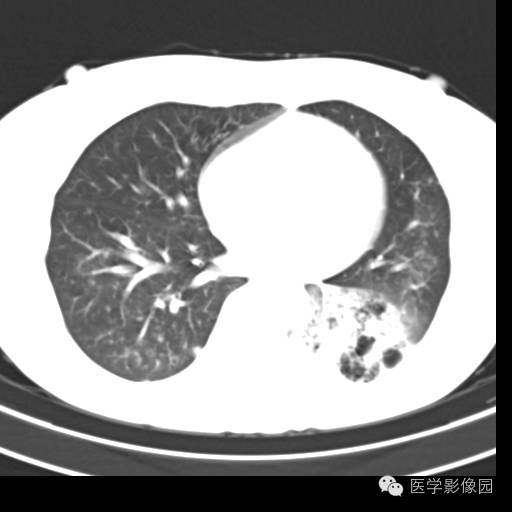

肺叶实变性支气管肺泡癌1例CT影像表现